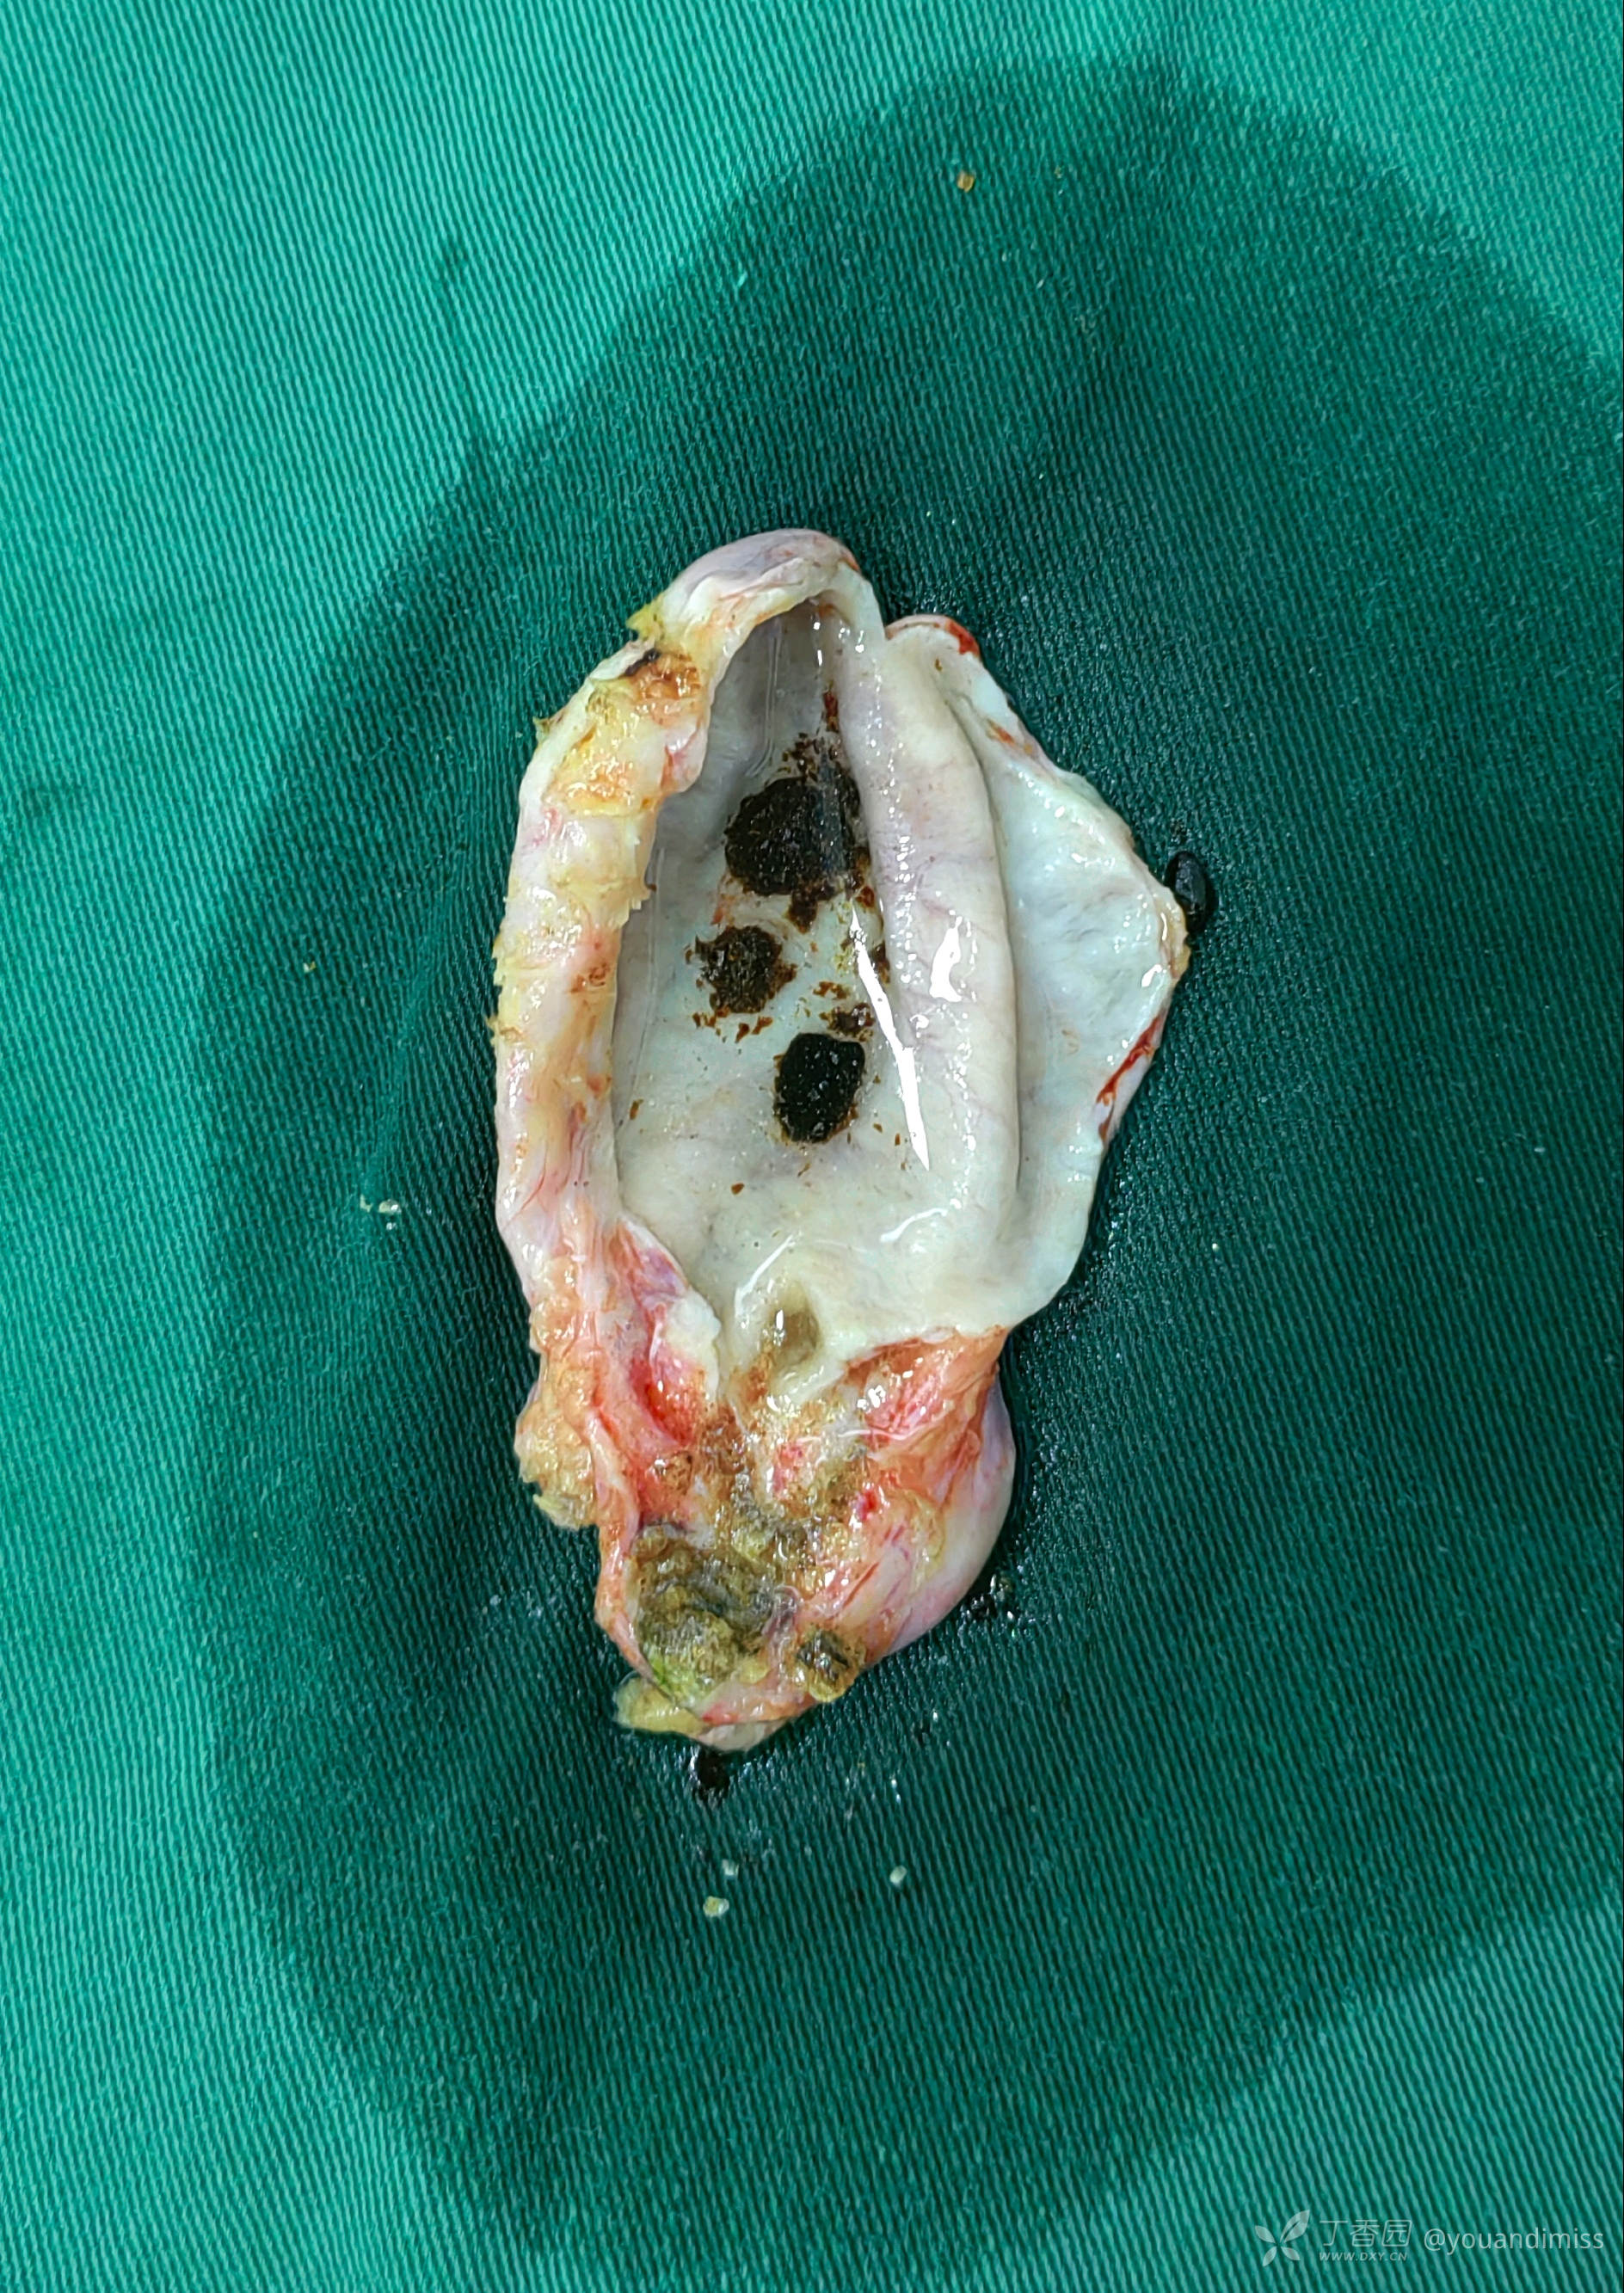

上图是胆囊标本,可触及一“豌豆”大小的质应结石,嵌顿于胆囊管内。

上图是剖开的胆囊标本,可见胆囊内结石,有一圆形黄色结石嵌顿于胆囊管内,胆囊内的胆汁成“水”样,无色透明,也就是俗称的“白胆汁”,是胆囊管闭锁或结石嵌顿所造成的。